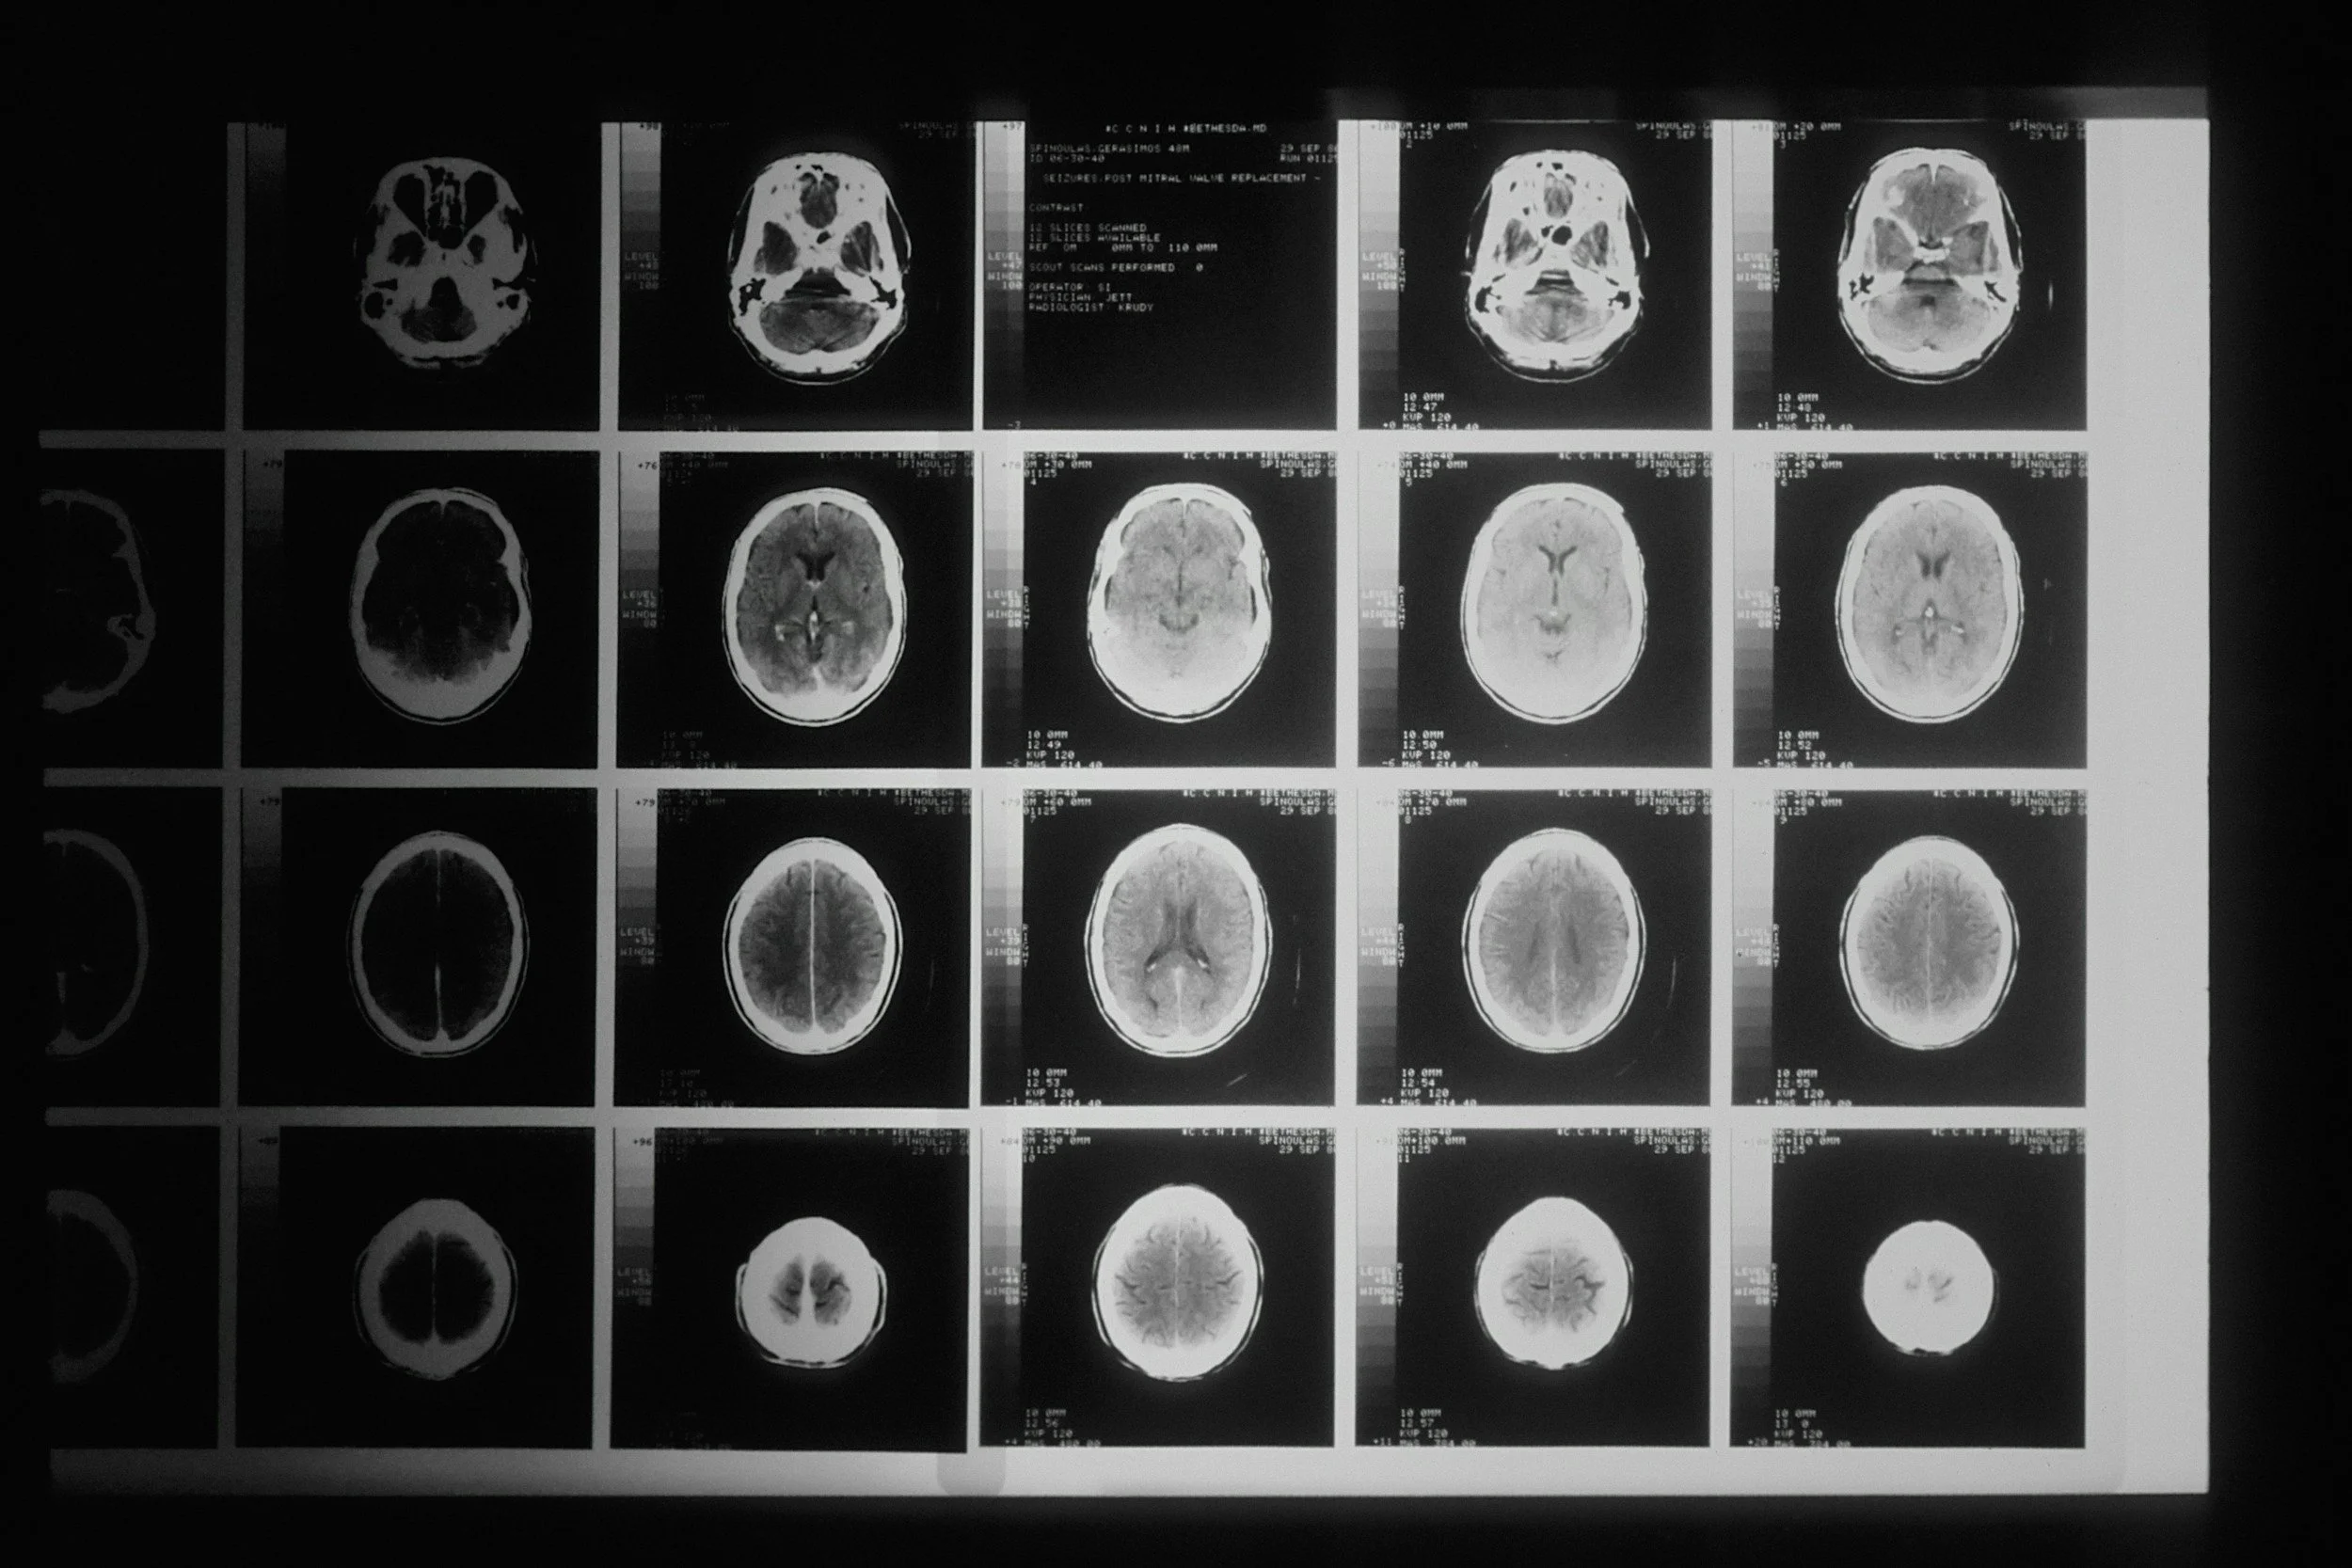

Concussion isn’t just a head knock. It’s a neurological, cognitive, and emotional disruption that impacts you far beyond symptoms.